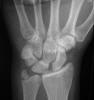

Scapholunate dissociation

Rupture of the scapholunate ligament

" Terry Thomas Sign"